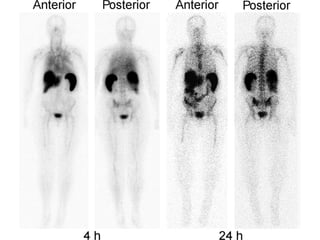

PET SCAN